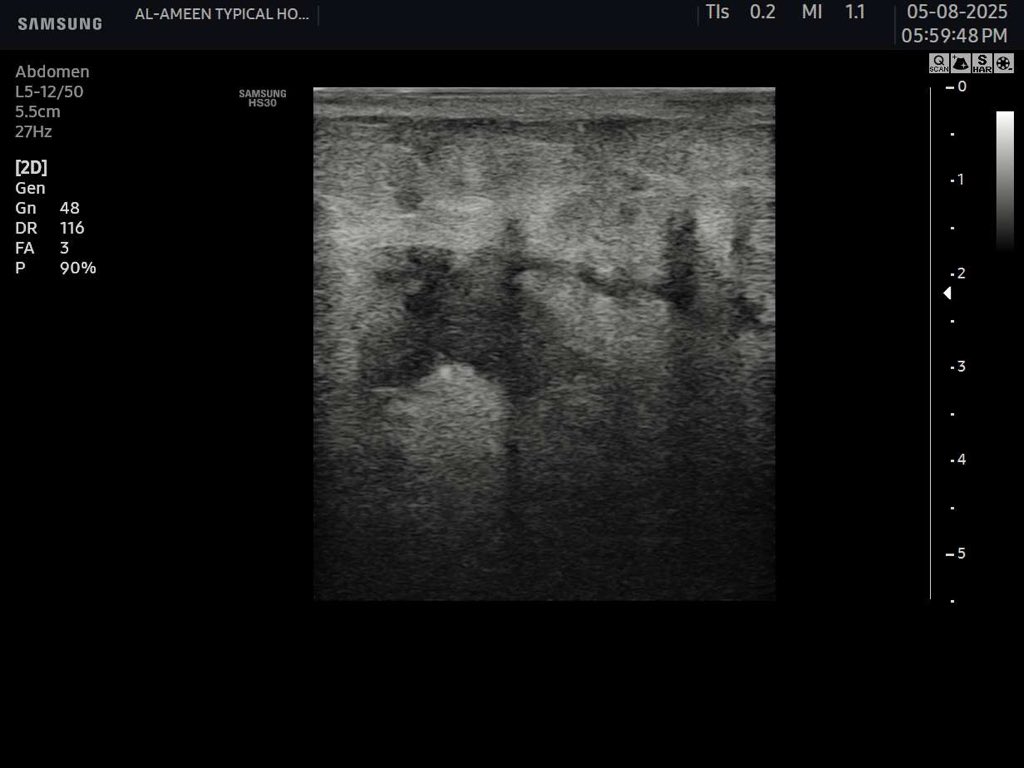

45 years female Presented with diffuse abdominal pain , persistent vomiting and bloody stool And a palpable abdominal mass seen to the RT of the umbilicus #EchoTech #Ultrasound #GIT

45 years female Presented with diffuse abdominal pain , persistent vomiting and bloody stool And a palpable abdominal mass seen to the RT of the umbilicus #EchoTech #Ultrasound #GIT

45 years female Presented with diffuse abdominal pain , persistent vomiting and bloody stool And a palpable abdominal mass seen to the RT of the umbilicus #EchoTech #Ultrasound #GIT